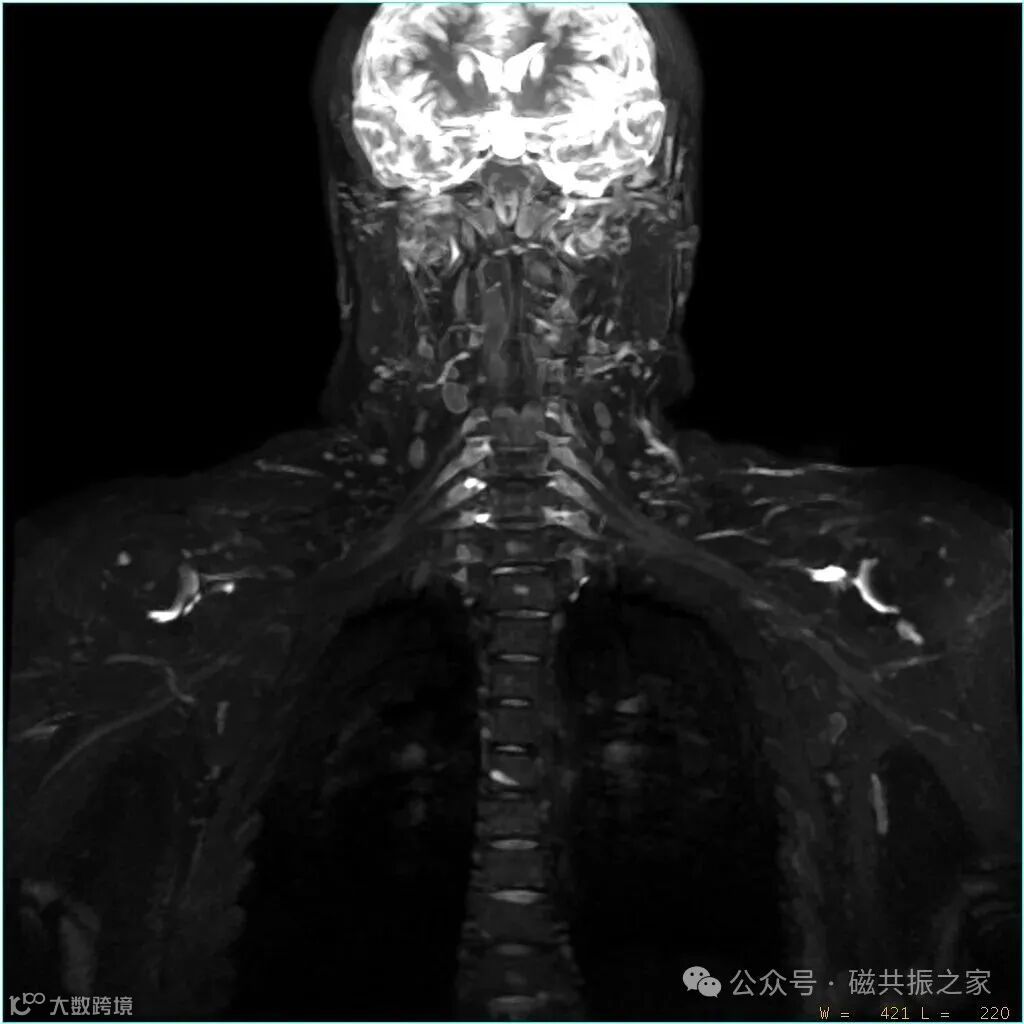

注射对比剂主要是为了更好的抑制淋巴结、流动缓慢血液的信号获得更干净的背景,上图△左,未注射对比剂;上图△右,注射对比剂。

注射对比剂结合3D STIR技术的均匀抑脂效果,消除背景干扰,可进一步突出神经结构。二者协同作用使得这种信号强度的巨大反差直接增强了神经与周围背景组织的对比度。最终实现臂丛神经与周围背景组织的高对比度清晰显示。